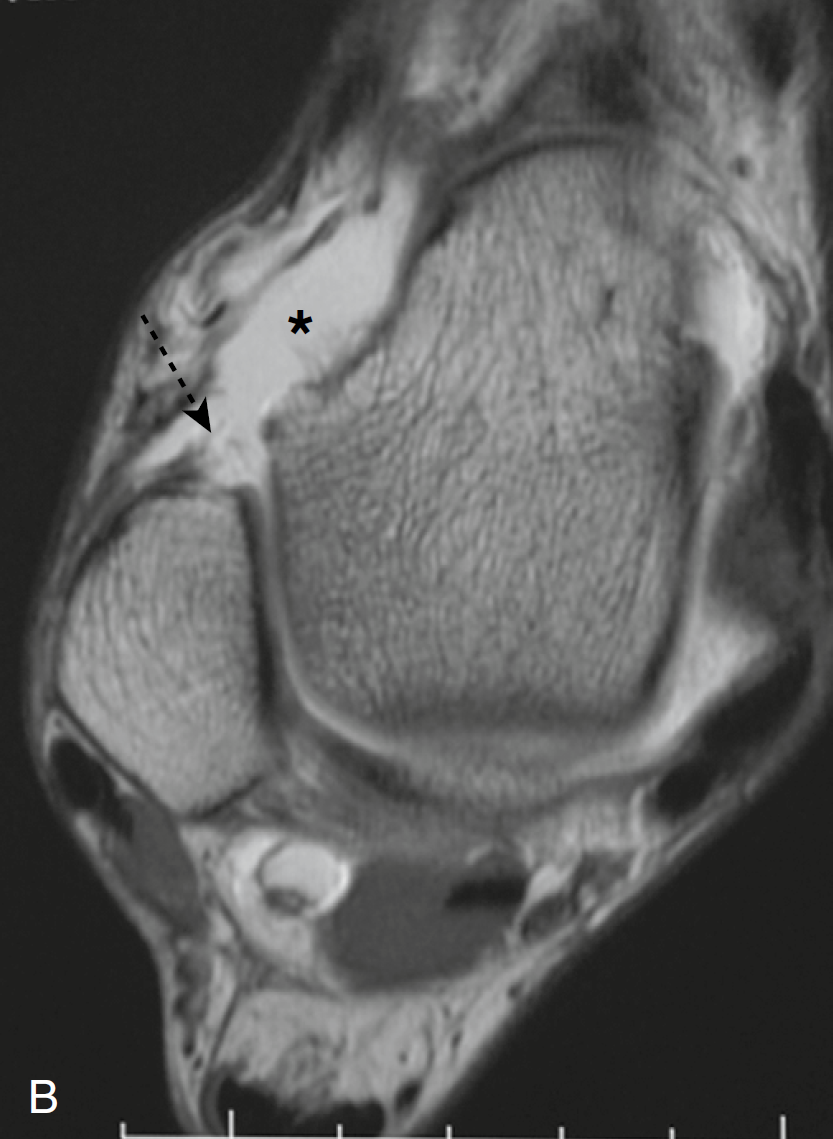

图1轴位T1加权的MR的关节造影图像:一个正常的、低信号强度距腓前韧带(箭头)